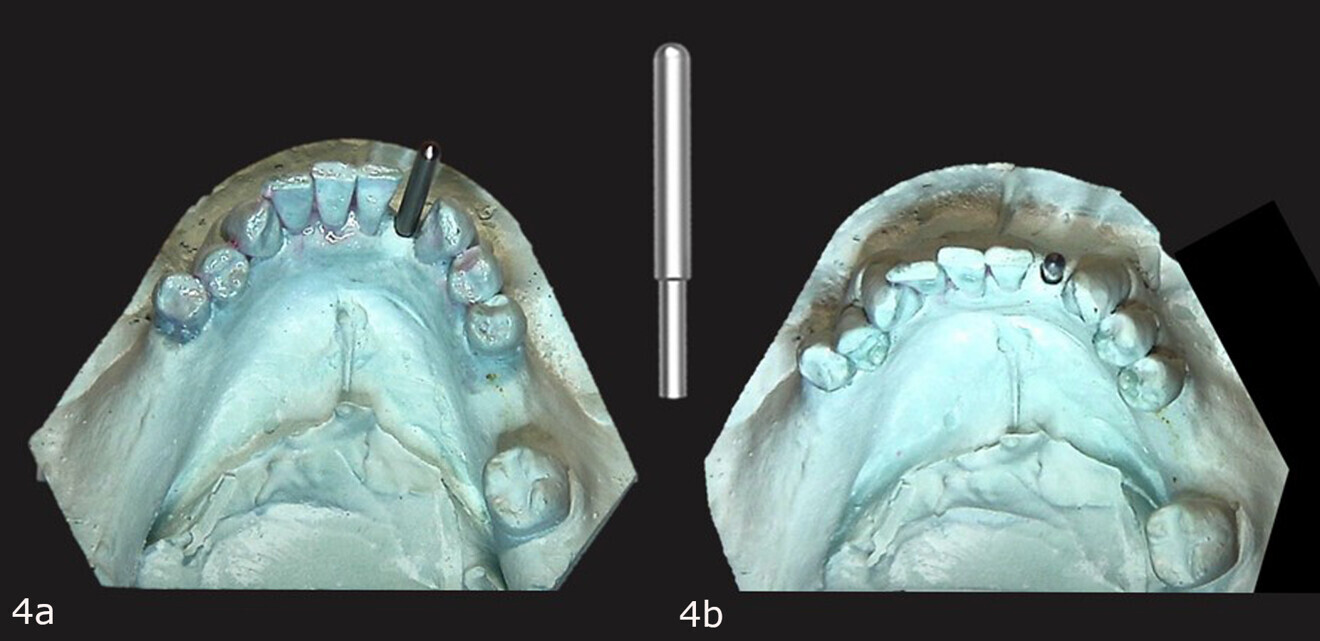

The conventional impression was utilised to create a stone cast to be used to fabricate a diagnostic guide. The 3/32 in. Guide Right pilot drill was utilised to create a guide hole in the planned implant site on the cast that was parallel to the adjacent teeth and centred in the extraction site (Fig. 3). A Guide Right one-piece guide post was inserted into the pilot hole on the cast (Fig. 4). Next, a Guide Right guide sleeve was inserted over the guide post with the retentive cleat positioned to the lingual aspect (Fig. 5). A light-polymerising resin (primopattern LC Gel, primotec) was placed over the cleat and then a roll of light-polymerising resin (primosplint, primotec) was placed on the lingual aspect of the teeth on the cast (Fig. 6). The resin was then pressed on to the lingual aspect of the teeth and the occlusal surfaces, light-polymerised and removed from the cast, creating the diagnostic guide (Fig. 7).

Figs. 4a & b: Guide post is inserted into the pilot hole made with the drill in the model (a & c). Guide Right guide post (b).